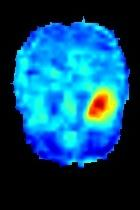

Current unsupervised anomaly localization approaches rely on generative models to learn the distribution of normal images, which is later used to identify potential anomalous regions derived from errors on the reconstructed images. However, a main limitation of nearly all prior literature is the need of employing anomalous images to set a class-specific threshold to locate the anomalies. This limits their usability in realistic scenarios, where only normal data is typically accessible. Despite this major drawback, only a handful of works have addressed this limitation, by integrating supervision on attention maps during training. In this work, we propose a novel formulation that does not require accessing images with abnormalities to define the threshold. Furthermore, and in contrast to very recent work, the proposed constraint is formulated in a more principled manner, leveraging well-known knowledge in constrained optimization. In particular, the equality constraint on the attention maps in prior work is replaced by an inequality constraint, which allows more flexibility. In addition, to address the limitations of penalty-based functions we employ an extension of the popular log-barrier methods to handle the constraint. Comprehensive experiments on the popular BRATS'19 dataset demonstrate that the proposed approach substantially outperforms relevant literature, establishing new state-of-the-art results for unsupervised lesion segmentation.